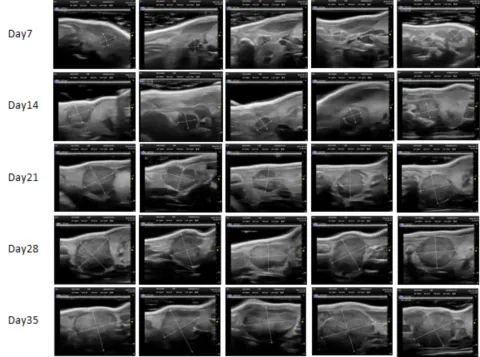

ʹÓó¬Éù¶àÆÕÀպͳ¬Éù»Ø²¨ÔÀí£¬£¬£¬£¬¿ÉÒÔÏÔʾ³ö¾Ö²¿ÓÐʵÖÊÐÔµÄÖ×Áö£¬£¬£¬£¬ÌØÊâÊÊÓÃÓÚÉöÔà¡¢ÒÈÏÙ¡¢Âѳ²¡¢°òë׵Ȳ¿Î»µÄÔλÖ×ÁöÄ£×Ó¼à²â¡£¡£¡£